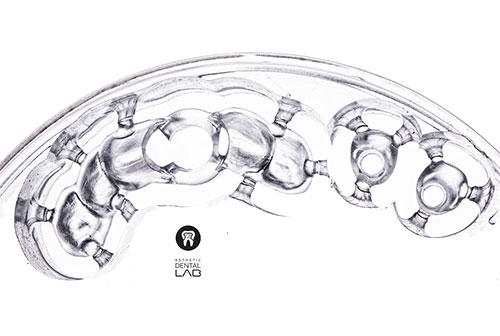

Laboratorio de excelencia, calidad y puntualidad, siempre hay buena comunicación. Trabajar con ellos es certeza de que habrá buenos resultados!★★★★★ Hace 8 meses -

El mejor lab con el que he trabajado en distintos niveles, resuelven tus dudas, hacen sugerencias, te ayudan con pedidos especiales y su equipo está en … More constante capacitación con lo mejor del continente. Si quieres poco o nulos ajustes, estética al 100 y subir de spec con tus pacientes es aquí, no me crean y vean sus rrss.★★★★★ Hace 8 meses -

Las restauraciones están muy bien adaptadas y en posición que no he tenido que hacer ningún solo ajuste a ninguna restauración. … More Ahorrando tiempo clínico.

Ya no puedo trabajar con otro lab después de conocerlos, son los mejores